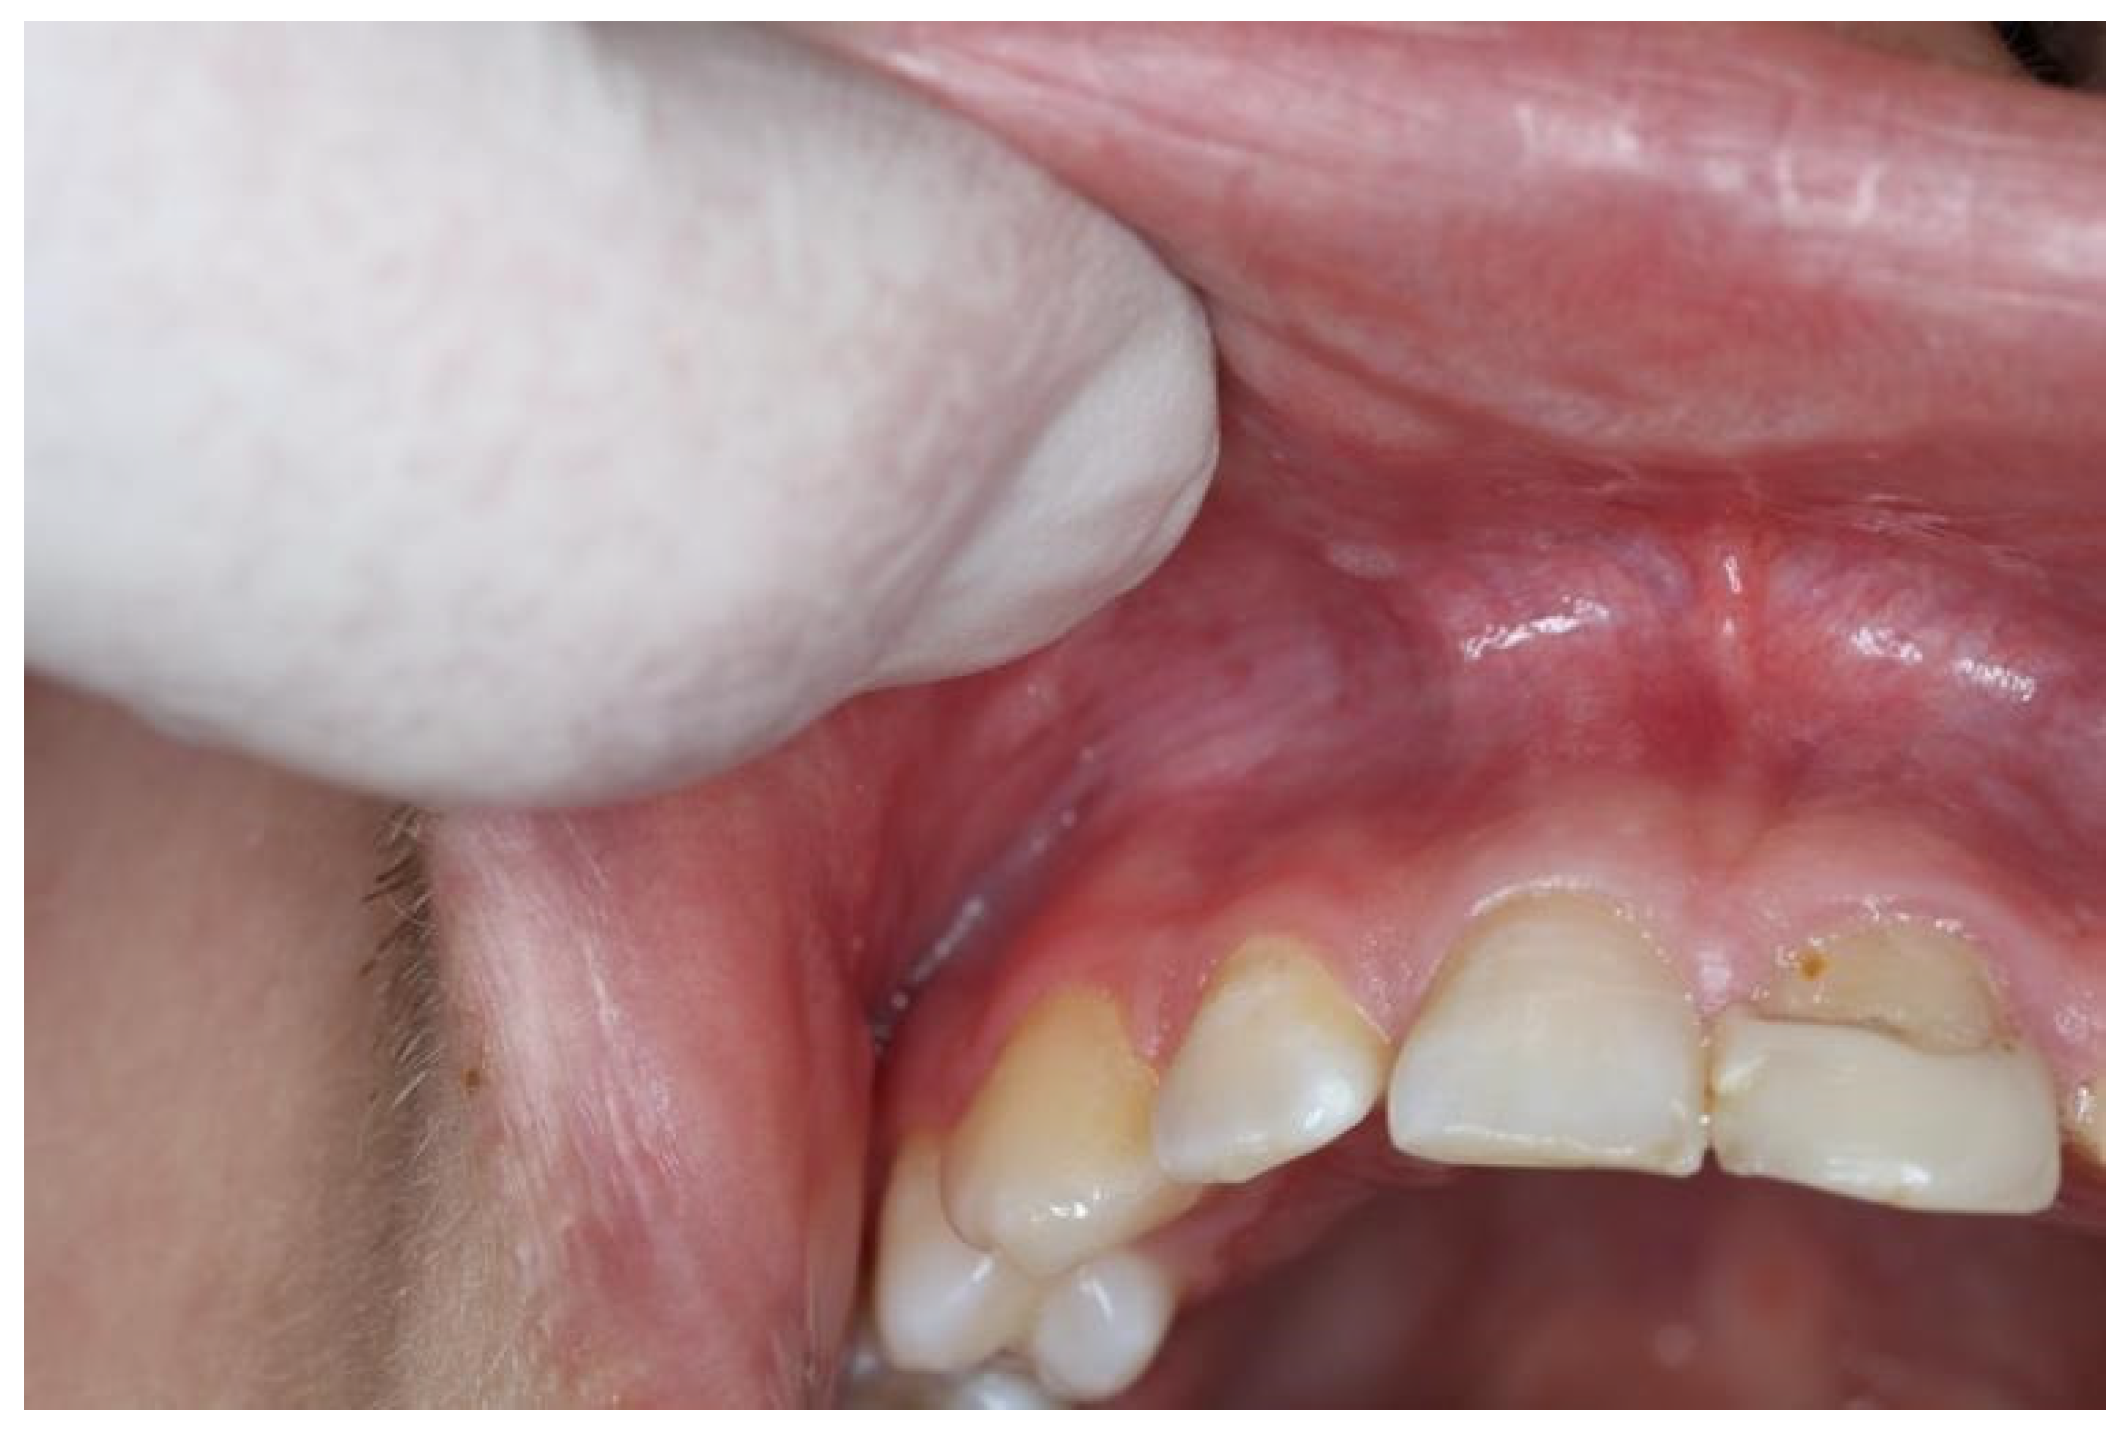

| Snus | 5–10 | 2–5 | White, grainy lesion (Figure 3) | Above tooth nr. 13/12 and 22/23 |